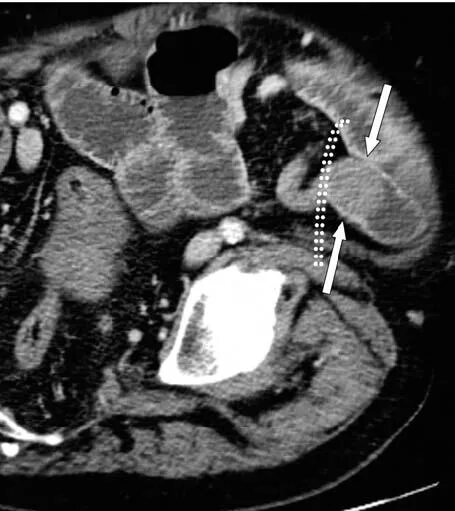

Непроходимость кишечника при онкологии